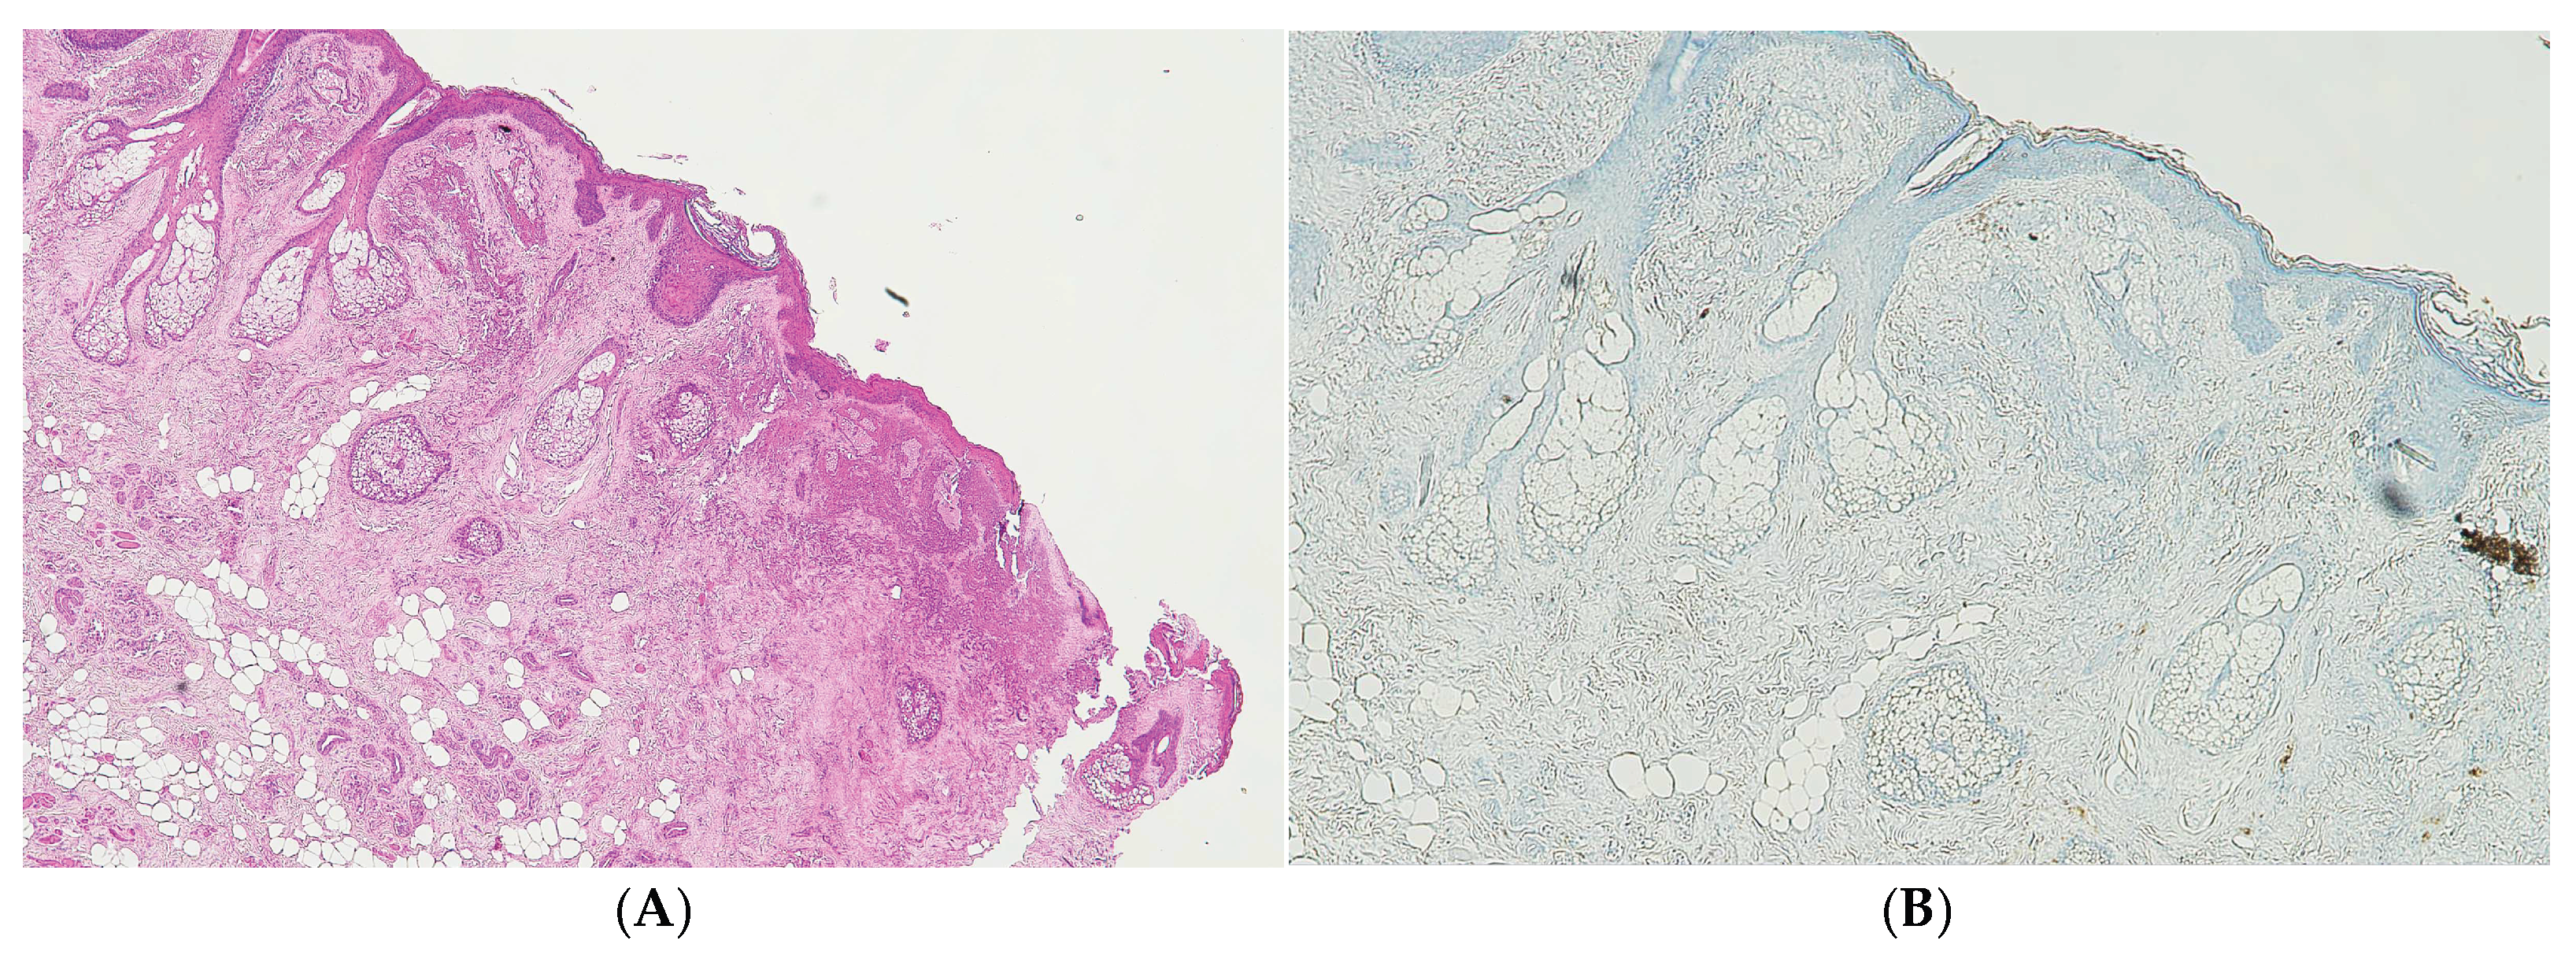

Figure 1. (A) Histological H&E staining of cutaneous tissue of a macroscopic area of discoloration in which Red Blood Cells (RBC) cannot be identified. (B) Immunohistochemical staining of cutaneous tissue with anti-GPA monoclonal antibody, positive for RBCs extravasation. The sample shows the presence RBCs in some of the areas that were marked as dubious in the H&E staining.

The initial histological investigation using H&E staining failed to reliably demonstrate the presence of extravasated red blood cells at the injury sites, a finding potentially interpreted as a lack of vital reaction. This absence was critically attributed to the severe cellular degradation and osmotic damage induced by the two freeze-thaw cycles. To definitively confirm the vital nature of the observed lesions—a distinction essential for forensic reconstruction—Immunohistochemical staining with anti-human Glycophorin A antibody was employed. The strong positivity observed across all sampled tissues (lips and cervical spinal cord) unequivocally confirmed the presence of antemortem hemorrhage.